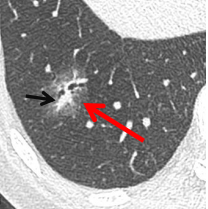

纯磨玻璃结节

混合性磨玻璃结节